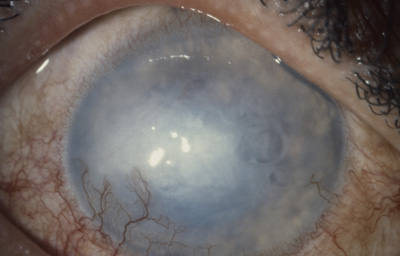

Al examen: Edema corneal con pliegues profundos, areas desepitelizadas y bullas, Endotelitis. Neovascularización corneal temporal inferior; Iris marrón blanquecino por pérdida marcada de pigmento, pupila de 5.0mm, opacidad en cápsula anterior. Tension Ocular digital media (Foto No 10).

Foto 10 - Foto inicial con bullas y neovascularización

Conducta: Decadron s/c cada 10 días( 6 amp), NaCl 3 al dia,, Maxidex 3 al dia, Atropina 1 al dia con controles cada 10 dias- Mas adelante Queratoplastia Penetrante.

Ultimo control a los 6 meses: Descompensación corneal, con reducción del area de leucoma; panus fantasma, despìgmentación del Iris, mantener Cetapred 2 al día y NaCl 3 al día- (Foto No 11) NO REGRESÓ

Foto 11 - Ojo mas tranquilo con descompensación corneal